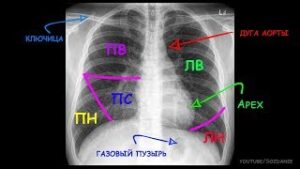

Одним из основных и самых простых методов диагностики различных заболеваний легких является флюорография. Исследование позволяет зарегистрировать патологические изменения строения основного органа дыхания, выявить туберкулез, рак легких, а также увидеть пневмонию. Это самый быстрый и дешевый способ диагностировать пневмонию и другие проблемы с легкими. Принцип исследования грудной клетки с помощью ФЛГ Флюорография — один из методов …